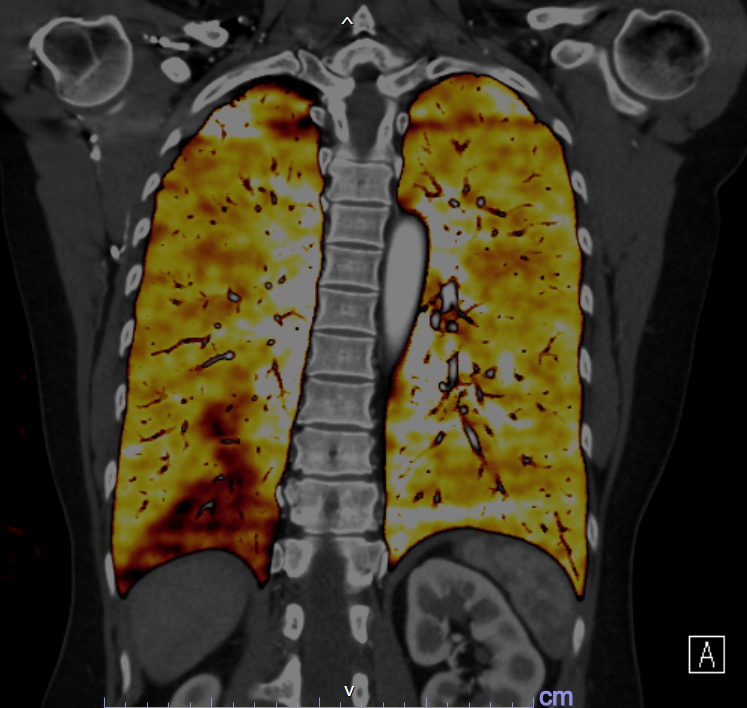

CT 検査(コンピューター断層撮影)

CT 検査とは X 線を回転させながら人体にあて、その情報を検出器で集めコンピューター処理をし、輪切りの写真や様々な方向の断層像を作り出す検査です。頭部、胸腹部、骨などを細かく検査することが出来ます。また脳血管、胸腹部大動脈、心臓・冠動脈などを三次元表示し、様々な角度から観察することもできます。

当院の CT は検出器が多列化した 64 列マルチスライス CT 2 台が稼動しています。従来の CT に比べ非常に高速な撮影が出来るため息止め時間が短く、全体の検査時間も短縮できます。

当院は 2022 年4月、機器更新に伴い新たに SIEMENS 社製 SOMATOM Drive を導入しました。2つの X 線発生装置を搭載しており、従来の CT に比べ非常に高速な撮影が出来るため息止め時間が短く、呼吸停止が難しい場合でも動きによるブレの少ない画像を撮像できます。また、新しい被曝低減技術により、さらなる被曝線量の低減を実現し、今までにない、様々な画像を作成できるようになりました。